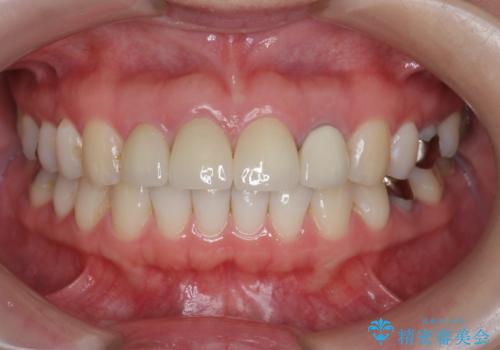

- 前歯を天然の歯のようにきれいにやりかえたいと希望され来院されました。

審美的なジルコニアクラウンを装着し、審美性が回復されたと満足いただくことができました。